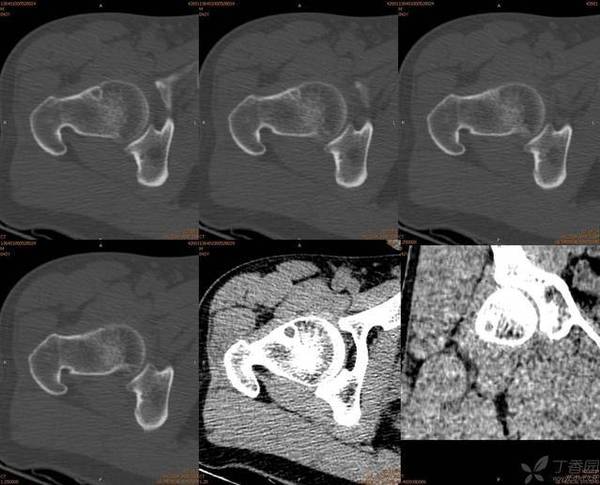

股骨颈疝窝

pittpit股骨颈疝窝